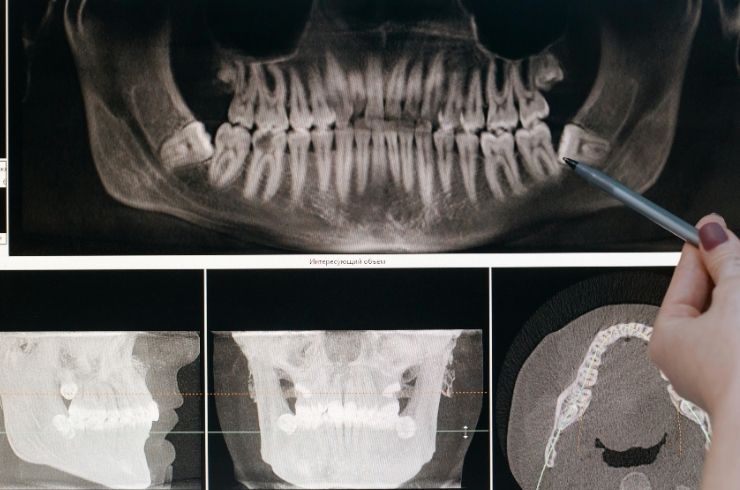

Dental imaging is an essential part of modern dentistry that helps in accurately diagnosing and planning treatments. It involves advanced techniques like digital X-rays and scans to get detailed views of teeth, gums, and underlying structures. At En-Brace Dental Clinics in Hyderabad, we use state-of-the-art imaging technology to detect issues that may not be visible during a regular examination, ensuring precise and effective treatment planning for every patient.

Choosing dental imaging in Hyderabad enhances the quality and accuracy of your dental care: